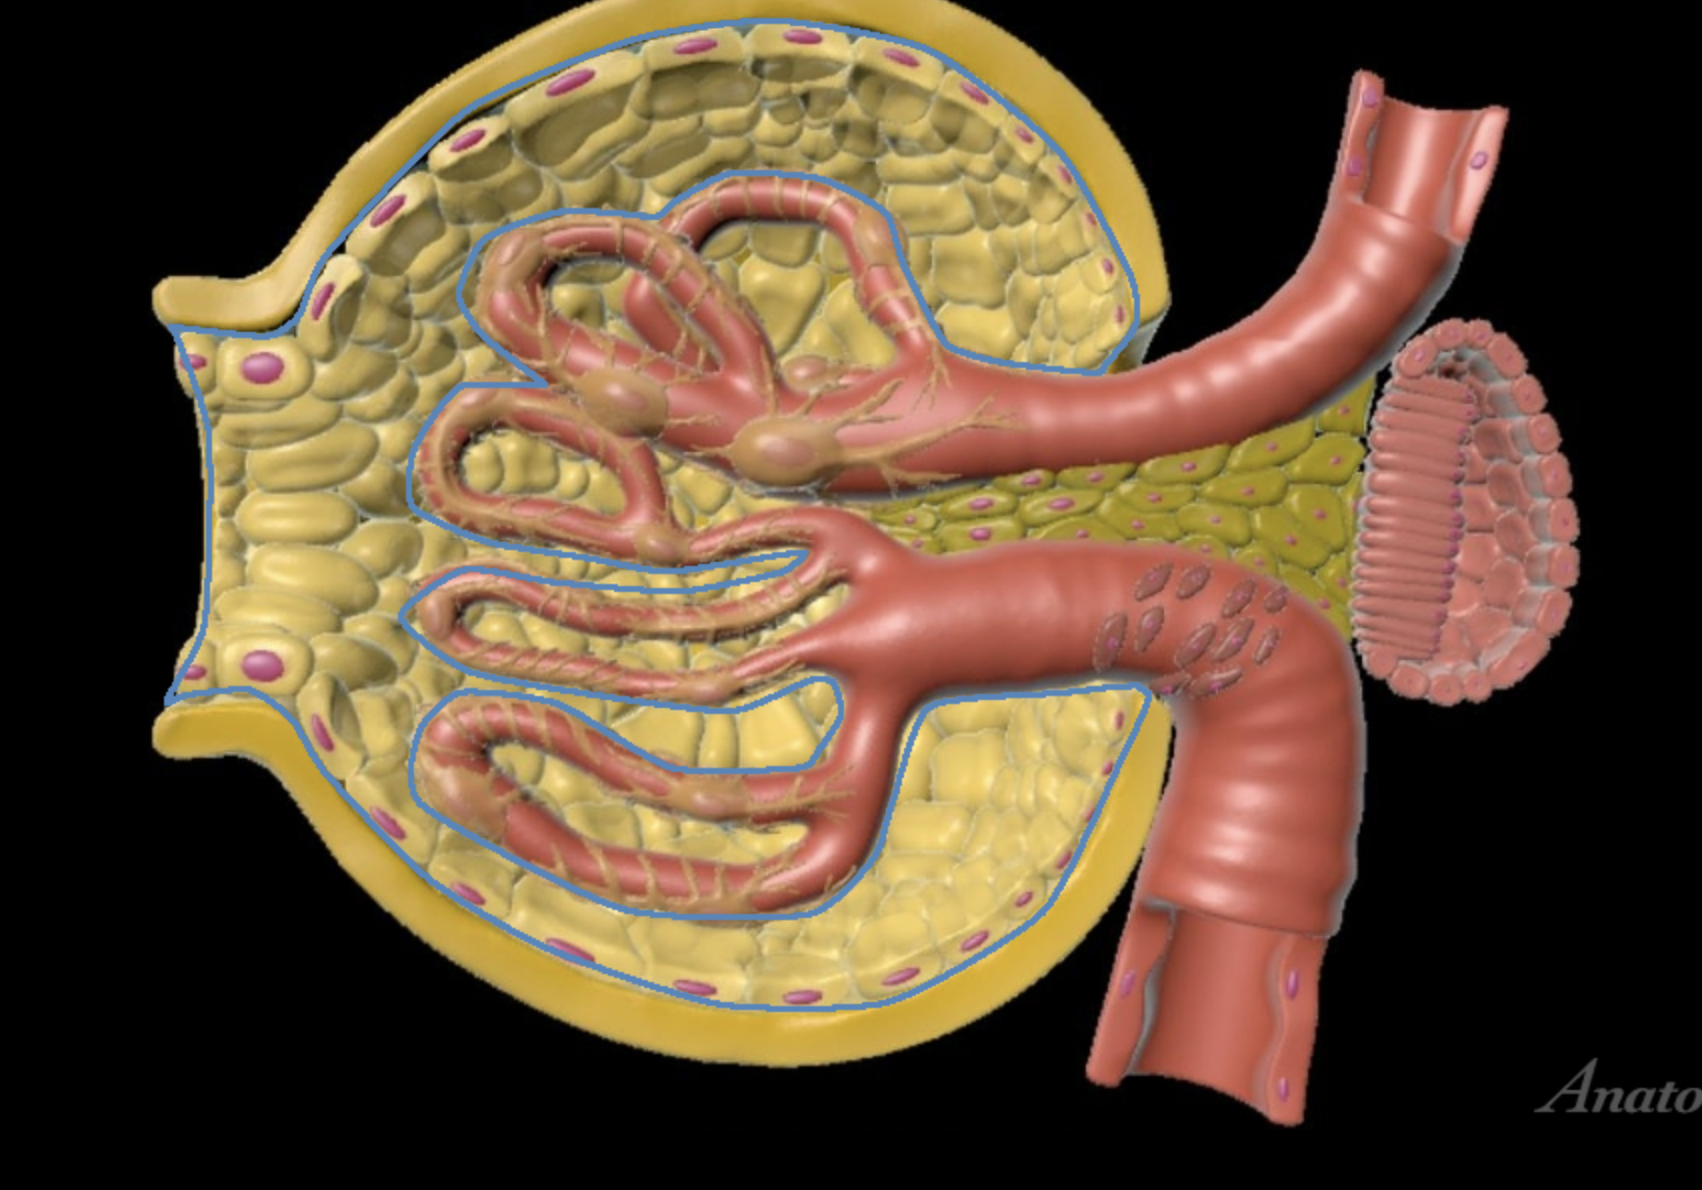

renal cortex

green

renal medulla

blue

renal columns

yellow

renal pyramids

purple

renal lobe

orange

renal papilla

minor calyx

teal

major calyces

renal pelvis

minor and major calyces